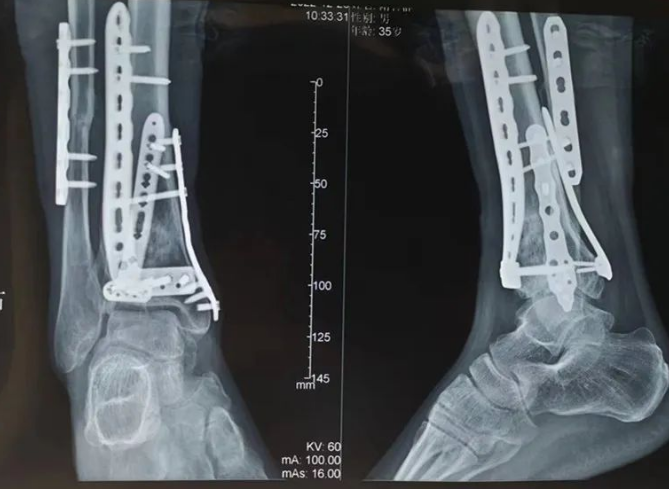

传统踝关节骨折金属内固定

使用可吸收钉板系统术后